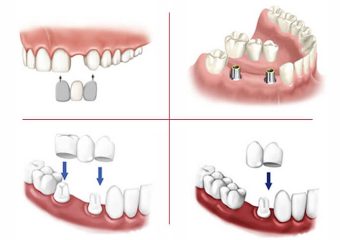

در این مقاله از سایت دکتر ندا مکانیک متخصص دندانپزشک اصفهان شما را با مزیت ها و معایب انواع بریج دندان آشنا میکنیم. تا پایان این مقاله همراه ما باشید. از بریجهای دندانی برای پل زدن در حد فاصله بین یک یا چند دندان از دست رفته استفاده میشود این پل توسط دندانهای طبیعی که در دو طرف دندان افتاده قرار دارند؛ پشتیبانی میشود سپس بسته به تعداد دندانهایی که جایشان خالی است. دندان مصنوعی ساخته شده و روی پلی که تعبیه شده است نصب میشود. دندانهای نگهدارنده در این عمل اباتمنت و دندانهای مصنوعی که در بین آنها قرار میگیرند پونتیک نام دارند.

بریجهای سنتی

این نوع بریجها متداولترین بریجهایی هستند که تا کنون در دنیا استفاده شدهاند و معمولاً از جنس سرامیک یا چینی متصل شده به فلز هستند.

بریجهای کانتیلور

این نوع پل مانند بریج سنتی نیست و استفاده از آن برای جایگزینی دندانهای انتهایی توصیه نمیشود. چرا که معمولا فشار زیادی روی این دندانها وجود دارد. در بریجهای کانتیلور (معلق) فقط از یک طرف دندان به عنوان لنگر یا پشتیبان استفاده میشود.

بریجهای مریلند

این بریجها از دندانهای چینی که روی یک چارچوب فلزی یا پلاستیکی کار گذاشته شدهاند ساخته میشوند. دندانهای موجود در هر دو طرف فضای خالی، به بالهای فلزی یا چینی موجود در بریج متصل میشوند.